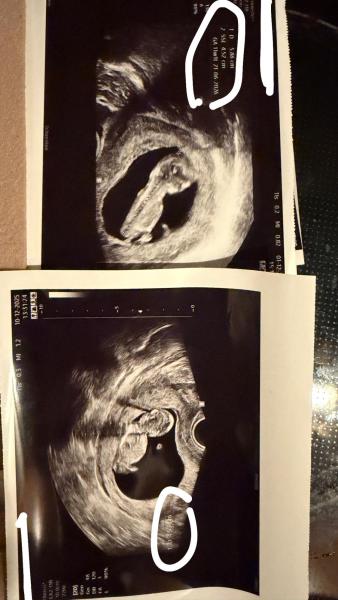

Hallo, ich war heute beim FA und dieser meinte alles okay. Jetzt frage ich mich, kann ein Arzt auch mal falsch schauen und das Herzchen schlägt doch nicht? Bin in der 12 SSW (11+5) ich habe es nämlich nicht gesehen..  Was mich wundert ich war an 10+3 dort und da stand 4,3cm und heute bei 11+5 stand 4,5cm.. Das hat mich später voll verwirrt, aber ich finde auf den Bildern liegt das Baby jeweils auch total anders. Kann es sein das es dann so wenig "wächst"? Ich sehe gerade das von heute die Beschriftung nur "D" ist nicht SSL. Aber wieso ist das D im ersten Bild von den cm deutlich größer als heute ? Ich hänge mal beide Bilder an.

Bild zu D Bedeutung - Forum für Juni - Mamis